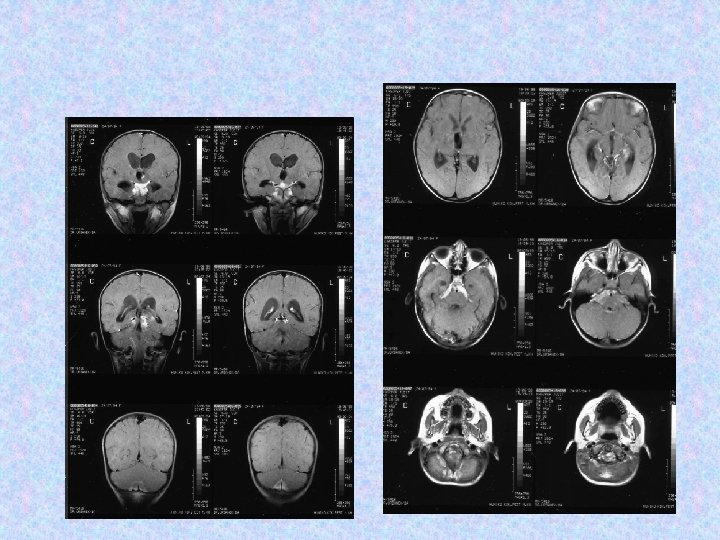

• A 2002. decemberi MRI felvételeken további progresszió figyelhető meg, a harmadik kamra területén és a bal kamraszarvban tumor igazolódott. Műtétet javasoltak, a szülők nem egyeztek bele, alternatív kezelést választottak. • A 2003. májusi és októberi MRI kontroll felvételek a harmadik kamrai tumor progresszióját és következményes, aszimmetrikus hydrocephalust mutattak. Műtét történt. Nem volt újabb neurológiai eltérés státuszában.

• 2003. október 30 -án transzkallózális, transzventrikuláris feltárásból részleges rezekció történt a harmadik kamrai tumorból. Az opus után nem alakult ki neurológiai novum, a posztoperatív kontrol CT normális volt. A szövettan pilocitás asztrocitómát igazolt. A posztoperatív időszakban hypernatrémia és egyéb ioneltérések miatt obszerválták. Solu-Cortefet kellett indítani. Endokrinológiai kivizsgálása elindult.

• 2004 januárjától endokrinológiai kezelés alatt áll. Centrális hypothyreózisa és hypadréniája miatt thyroxin és kortizol szubsztitúciót kap. • A 2004. augusztusi és decemberi kontrol MRI további tumor progressziót mutatott a hátsó scala területén, újabb neurológiai jel nem alakult ki.

• A klinikai folyamat eseménytelen volt 2005. áprilisáig, ekkor újból jelentkeztek fejfájásai és reggeli hányásai. Enyhe cerebelláris tünetek is kialakultak. • 2005. április 7 -én szuboccipitális rekraniotómia történt. Makroszkóposan totális eltávolításra került a kisagy bal féltekei, a negyedik agykamrai, és a bal oldali pontocerebelláris tumor. Továbbá intraoperatívan tumor disszemináció látszott a szubarachnoideális térben. Szövettan pilocitás asztrocitóma.